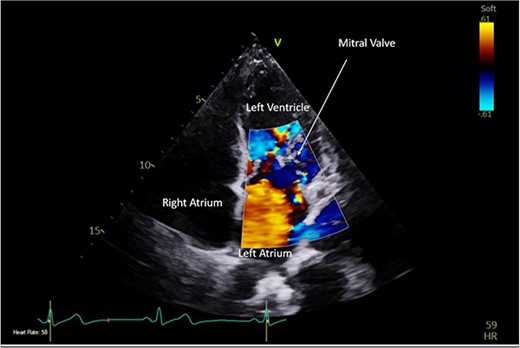

A CTPA was undertaken on Day 2, which excluded pulmonary embolism but confirmed bilateral peri-hilar consolidation and pleural effusions consistent with pneumonia. However, her pulmonary artery was dilated at 32 mm indicative of potential heart failure. On Day 5 of her ICU stay, a transthoracic echocardiogram was undertaken that revealed there to be severe mitral regurgitation including a mobile echogenic mass attached to the underside of the anterior mitral valve leaflet consistent with a vegetation (Figs 1 and 2).

Pre-operative TTE with Doppler depicting mitral valve with vegetation (labelled).